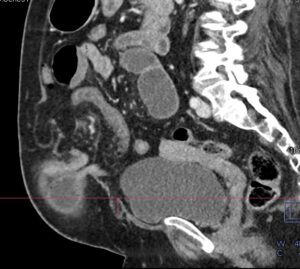

HALLAZGOS RADIOLÓGICOS